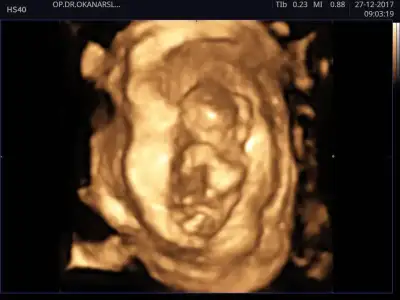

Merhaba, ultrason görüntülerinde sat'a göre 11+4 üz.

cinsiyet tahmini yapabilecek olan var mı:)

IMG_4481.webp IMG_4475.webp IMG_4476.webp IMG_4483.webp